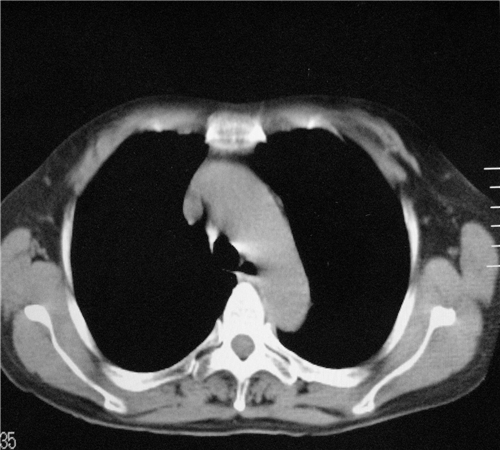

标题: CT26849:女67岁反复胸痛两天余,临床考虑夹层。 [打印本页]

标题: CT26849:女67岁反复胸痛两天余,临床考虑夹层。

右肺感染,未见夹层。

既然考虑夹层,建议强化!另:右下肺感染!

1)右肺感染性病变。2)建议行ct增强扫描或mri检查排除主动脉夹层。

双下肺感染,右侧显著。有无夹层,增强扫描后再诊断。

1. 感染性病变,2.未见夹层,3.食道未见异常。

1.考虑双肺感染,右侧为重;2.建议ct增强或mri排除主动脉夹层

双下肺感染,右侧显著。有无夹层,增强扫描后再诊断。食道未见异常。

平扫未见确切夹层征,建议必要时增强扫描或mri检查。